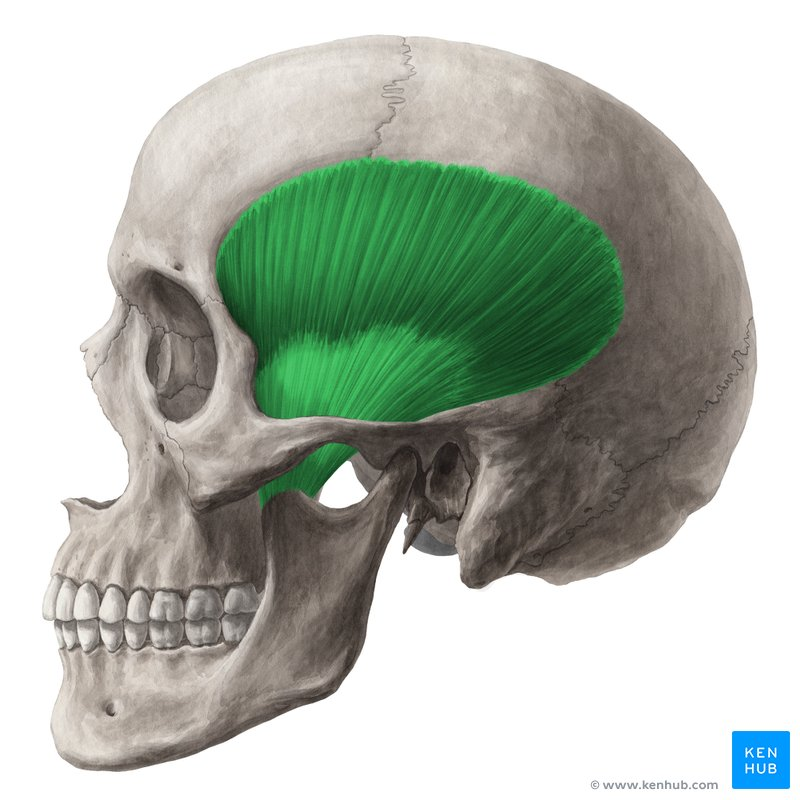

m temporalis